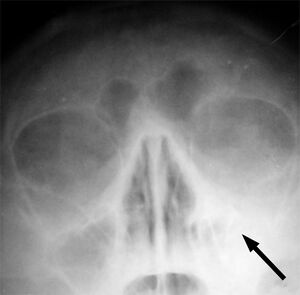

![]() | |

يشير السهم إلى منطقة الالتهاب في جيوب الفك العلوي في الجانب الأيسر من الوجه. لاحظ أن المنطقة التى يشير لها السهم ليست شفافه لقلة الهواء فيها، مما يشير إلى امتلائها بالسوائل بالمقارنه مع الجانب الآخر من الوجه. | |